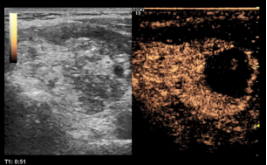

图 超声引导下甲状腺左叶实性结节穿刺活检+微波消融治疗

图 术后复查超声及超声造影,超声显示术区及其周围未见出血,甲状腺左叶实性结节呈消融术后改变